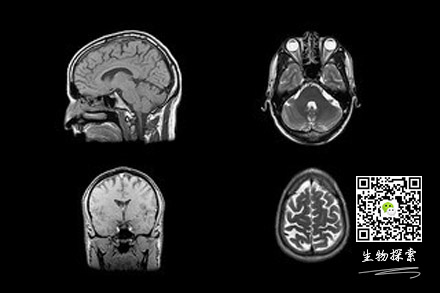

科学家通过脑成像研究发现,和正常手一样,“外来手”的动作也是伴随着大脑初级运动皮层(大脑控制躯体运动的关键部位)的活动产生。但是大脑运动前皮层(发挥运动规划作用的部位)却没有对外来手的动作进行运动规划。因此,那些两侧大脑半球之间联系曾被切断的患者,有可能因运动程序被打乱从而患上外来手综合症。